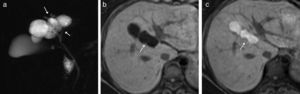

Varón de 40 años con colangiocarcinoma perihiliar tipo IIIb con crecimiento periductal-infiltrante. A) Imagen transversal de TC hepático con contraste que muestra engrosamiento y estenosis del conducto hepático izquierdo (flecha). B) Plano coronal de TC con engrosamiento del conducto hepático izquierdo y contacto cincunferencial con una rama portal por invasión (flecha) y dilatación de la vía biliar intrahepática (asterisco). C) RM eco de gradiente T1 con contraste que muestra dilatación de la vía biliar y atrofia lobar por invasión vascular (asterisco).

Varón de 78 años con colangiocarcinoma perihiliar tipo iv. A) TC coronal con contraste en fase portal en la que se observa un engrosamiento de la pared de la vía biliar extrahepática y masa (flecha) que invade estructuras periductales por crecimiento mixto, periductal-infiltrante y expansivo. B) Colangio-RM 2D en el plano coronal que muestra la oclusión de la luz (flecha) de la vía biliar; vesícula (estrella). C) Colangio-RM 2D en el plano transversal que muestra la extensión longitudinal hasta los conductos secundarios (flechas curvas).